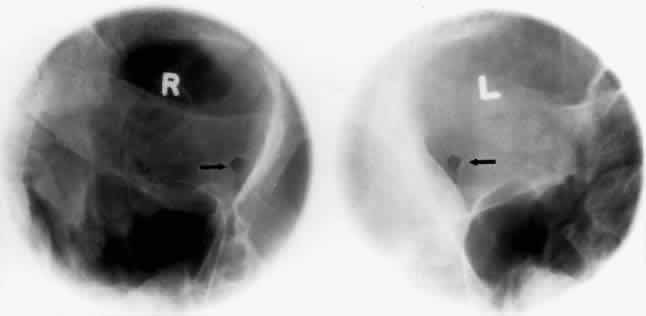

The optic foramen should measure 6 mm vertically and 5 mm horizontally. Asymmetry greater than 1 mm or a vertical dimension greater than 6.5 mm is considered abnormal.15,27 Ninety-eight percent of patients have optic canals that vary by less than 1 mm.27 Concentric enlargement of the foramen and optic canal can be seen with optic nerve gliomas, meningiomas, neurofibromatosis, and less commonly an aneurysm of the ophthalmic artery (Fig. 16). A decrease in the optic foramen and canal dimension can be seen in fibrous dysplasia, Paget's disease, hyperostosis secondary to a meningioma, or microphthalmos (Fig. 17, Table 1).

Fig. 16. Oblique apical projections showing the optic foramen. The left optic foramen has concentric enlargement from an optic nerve glioma. The foramen should not have greater than 1 mm of asymmetry.